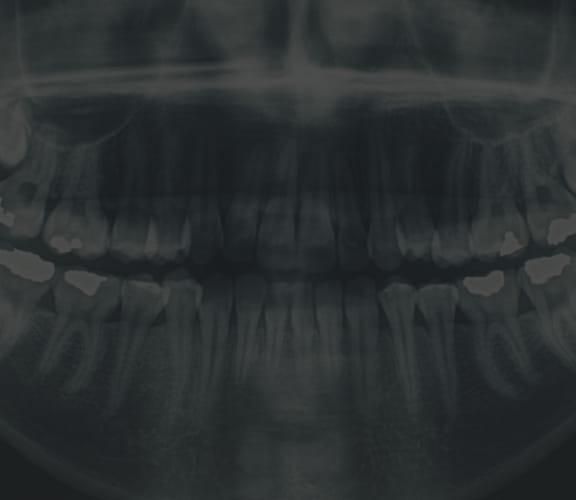

Tooth Extraction

When the extraction of a tooth is required:

- An incision in the gums is made

- The tooth is removed

- The area is stitched up and is allowed to heal

During this time, it is important to think about a tooth replacement option. An extracted tooth leaves an open area in the jaw which, in time, allows the neighboring teeth to drift into the area where the tooth was extracted. This in turn, causes a chain reaction to all the surrounding teeth. Also, if you are considering placing an implant in the future, you should consider asking your dentist to place a bone graft at the time of surgery to preserve the bone width and height.